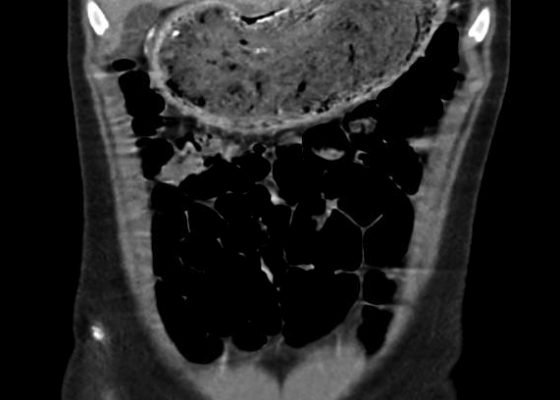

Gastric Bezoar

DOI: https://doi.org/10.21980/J85K5WIn the abdominal radiograph, a nonspecific and non-obstructive bowel gas pattern with no air-fluid level was noted, however the stomach was distended with soft tissue. The CT abdomen/pelvis revealed a distended stomach with undigested heterogeneous contents (presumed bezoar).